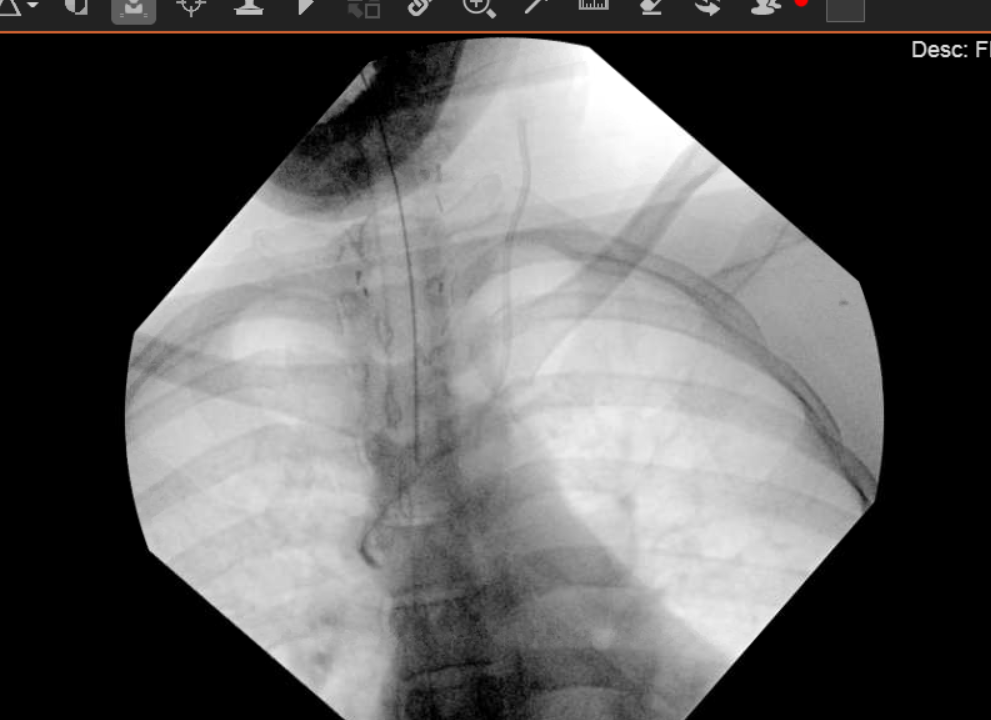

Initial image shows line seemingly well positioned but with an odd angulation to the tip of the line and just lateral to the R mainstem bronchus - possible appearance for azygous placement. Introduced a 0.032" wire under fluoro to try and reposition and... the wire goes straight to the RA. Hard to tell if the line was in the azygous and popped out when I introduced the wire or if it was never there to begin with.